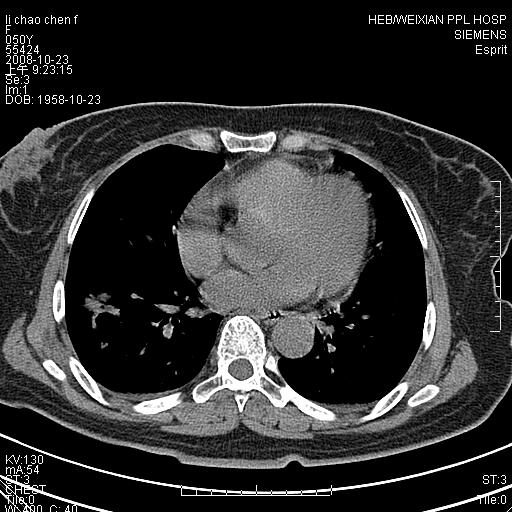

体检发现肺部肿块,现无不适。五年前曾有过哮喘病史。

强化扫描后病灶几乎无增强,强化后的病灶看起来密度虽高,是我为了清晰改变了窗宽窗位。(有点弄巧呈拙)

先对现有的图象资料谈几点看法:病变位于右肺下叶前基底段,上部呈类圆形改变,分叶及毛刺征象不明显,下部呈不规则气腔改变,近肺门侧可见与一粗大血管相连,考虑为引流静脉影.其他肺叶相对正常所见.分析:该病灶良恶性均有可能.(现有资料来说).强化及穿刺活检有助鉴别.

术后冰冻切片怀疑是细支气管肺泡癌,等病理结果。